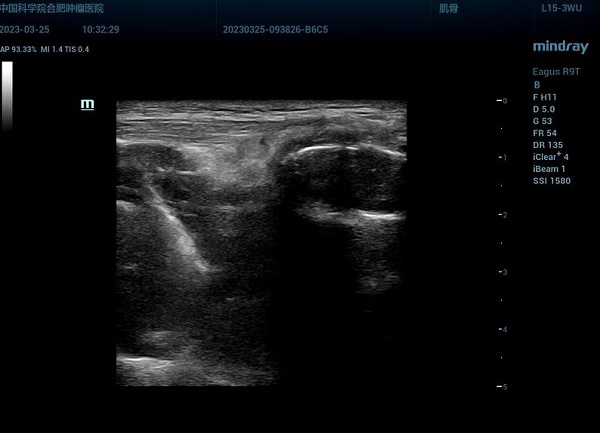

经介入超声专家反复探查,观察肿物及与周围重要脏器的关系,终于在胸骨旁肋间隙,内乳动脉旁,寻找到一条狭窄的安全穿刺通路,通路直径仅5mm,在超声实时引导下使用17G同轴针经皮穿刺准确进入肿块内,用18G自动活检针取出4条白色鱼肉状肿瘤组织条,穿刺顺利,术后未出现明显并发症。病理结果显示,为低分化鳞状细胞癌,结合免疫组化标记,符合胸腺来源。

超声引导下穿刺画面